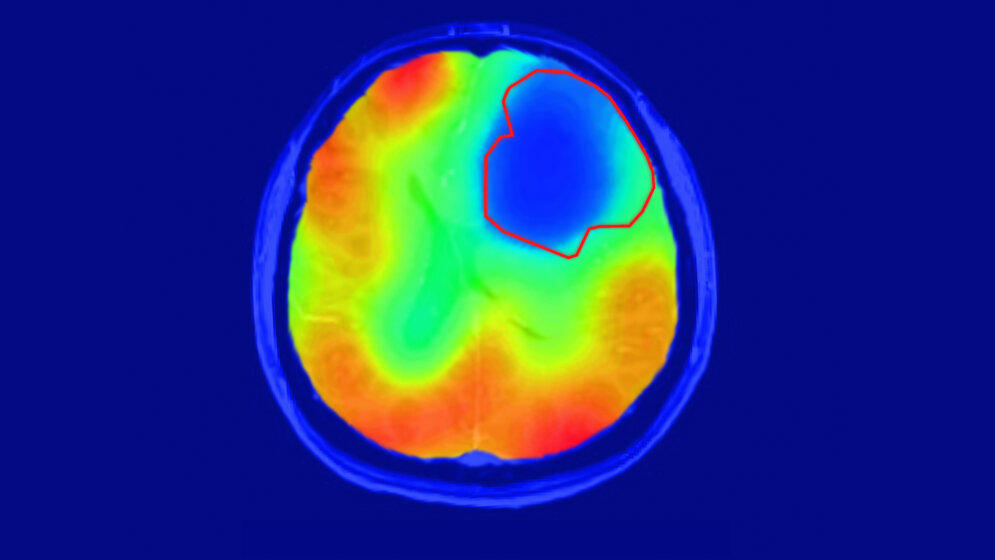

Die neue Technik der DKFZ-Forscher kommt ganz ohne Radioaktivität aus und zeigt zudem sehr spezifisch den Sauerstoff-abhängigen Stoffwechsel des Gewebes. Die Wissenschaftler verwenden eine stabile, nicht radioaktive Variante des Sauerstoffs, 17O2, die in geringen Mengen auch in der Atemluft vorkommt. Die Probanden atmen diesen besonderen Sauerstoff in angereicherter Form ein. Überall, wo in den Körpergeweben Sauerstoff verstoffwechselt wird, geht 17O2 eine Verbindung mit Wasserstoff ein. Dadurch wird es im Magnetfeld des MRT nachweisbar. Gewebe, das viel Sauerstoff umsetzt, erscheint daher im Bild hell.

Die DKFZ-Wissenschaftler um Paech und seinen Kollegen Sebastian Niesporek haben das Prinzip zunächst bei drei gesunden Probanden durchgespielt. Wie erwartet lassen deren Gehirne in der Bildgebung einen hohen Sauerstoffumsatz erkennen. Dann untersuchten die Forscher zehn Probanden, bei denen ein Gehirntumor diagnostiziert worden war, mit der neuen Sauerstoff-MRT. „Das Ergebnis war wirklich eindrücklich: Die Tumoren erschienen im Bild als dunkle Flecken, weil hier kein Stoffwechsel mit Sauerstoff stattfand“, schildert Paech. „Uns hat überrascht, dass dies sowohl bei höhergradigen aggressiven Tumoren als auch bei weniger aggressiven niedriggradigen Tumoren der Fall war.“ Bislang war nicht klar, ob der Warburg-Effekt auch bei niedriggradigen Hirntumoren gleichermaßen eine Rolle spielt.

Damit haben die DKFZ-Forscher nicht nur neue Erkenntnisse über die Biologie von Gehirntumoren gewonnen. Sie haben auch eine Technik in der Hand, die das Zeug für eine verbesserte Charakterisierung von Tumorgeweben hat. „Wir sehen das Verfahren als ergänzend zur strukturellen MRT-Bildgebung, um Unterschiede zwischen Tumor und gesundem Gewebe auszumachen“, so Paech. „Die zusätzlichen Informationen könnten künftig dabei helfen, Tumoren anhand ihres besonderen Stoffwechsels noch präziser zu charakterisieren.“